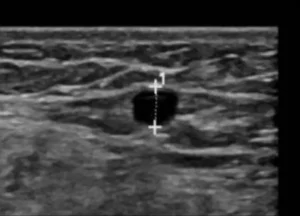

Vein mapping uses ultrasound imaging to see inside your blood vessels. This test creates a map of your arteries and veins and any blockages, if any. Usually a vein mapping test is ordered before vein procedures to check for health conditions that affect your blood vessels.